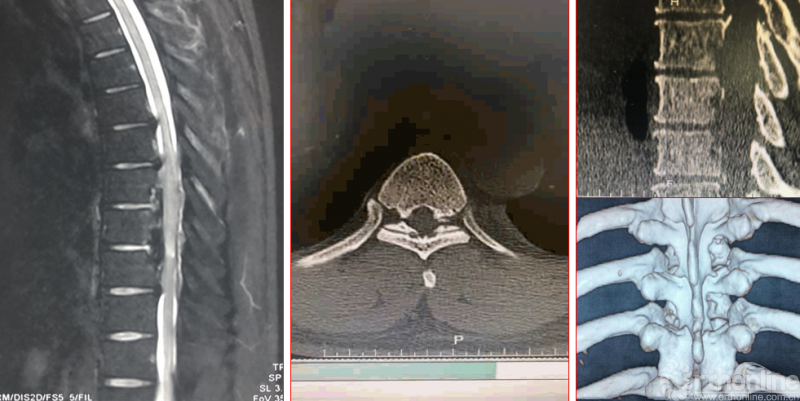

术前资料

影像学资料